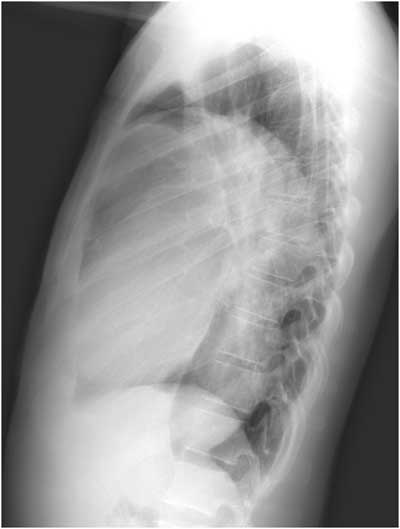

There is no air-fluid level seen on either view to support the diagnosis of pleural effusion, and the lateral view clearly demonstrates a mass-like lesion, the epicenter of which lies in the anterior mediastinum. Developing a differential for a mediastinal mass requires understanding its boundaries and divisions. The boundaries of the mediastinum itself are the thoracic inlet, the diaphragm, and the pleural sacs. The anterior division of the mediastinum extends from the sternum to the pericardium and brachiocephalic vessels, the posterior division extends from the pericardium and trachea to the vertebral column, and the middle division fills the space between the anterior and posterior mediastinum (Table 1)(5). This patient presented with an anterior mediastinal mass, the most common of which are thymomas, teratomas, thyroid malignancies, and lymphomas. Of these, thymoma has the highest incidence, representing 50% of all anterior mediastinal neoplasms in adults. Thymomas most often develop between the ages of 40-60 and only a third of patients will develop symptoms directly related to the tumor’s effects on surrounding structures. As a result, the diagnosis is often made as an incidental finding on a chest radiograph obtained for other causes. Most thymomas are indolent tumors, which may appear solid, cystic, or hemorrhagic on computed tomography, and up to 50% of thymomas will demonstrate some sort of paraneoplastic syndrome. Distant metastases are uncommon (<7%); however, local invasion can occur up to 32% of the time (5-8).